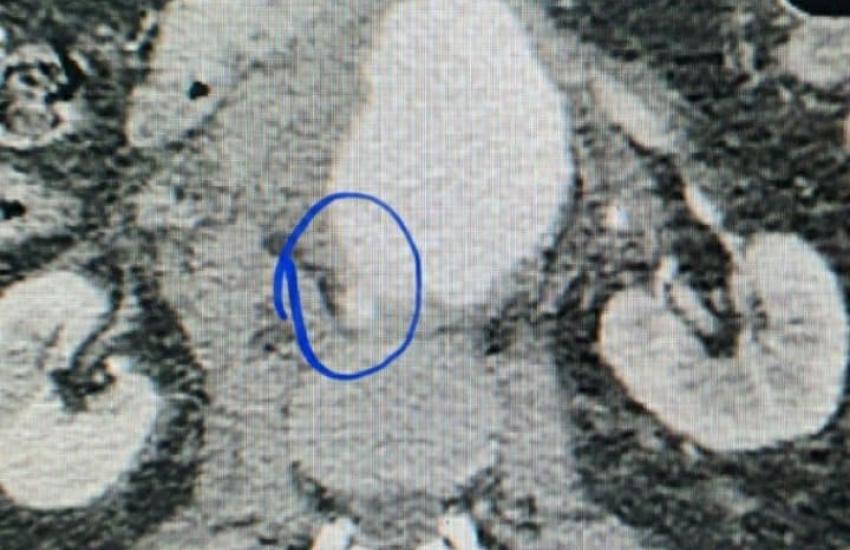

По приїзду в обласну лікарню хворому одразу зробили КТ, зібрали консиліум лікарів. Встановлений діагноз: атеросклеротична аневризма черевного відділу аорти з розривом. Прийняте рішення про оперативне втручання. Лікарям одразу стало зрозуміло, що операція буде дуже складною через те, що аневризма розпочиналася від рівня відходження ниркових артерій і закінчувалася біфуркацією аорти. Це потребувало високого перетискання аорти під час операції над рівнем ниркових артерій, виключення нирки із загального кровотоку. Черкаські хірурги звернулися за допомогою до своїх колег Олександра Ліксунова та Андрія Ратушнюка з Національного інституту хірургії та трансплантології ім. О.О. Шалімова. Незважаючи на те, що київські колеги щойно повернулися в Київ з Миколаєва, вони вже на ранок вирушили до Черкас, адже, рятувати чоловіка потрібно було в найкоротший термін.

14 жовтня 2020 пацієнту було проведене оперативне втручання – видалення аневризми з заміщенням її судинним протезом. Операція потребувала відключення кровотоку в нирках на 25 хв, була складною та тривала 2 години. Вона пройшла успішно та без ускладнень.